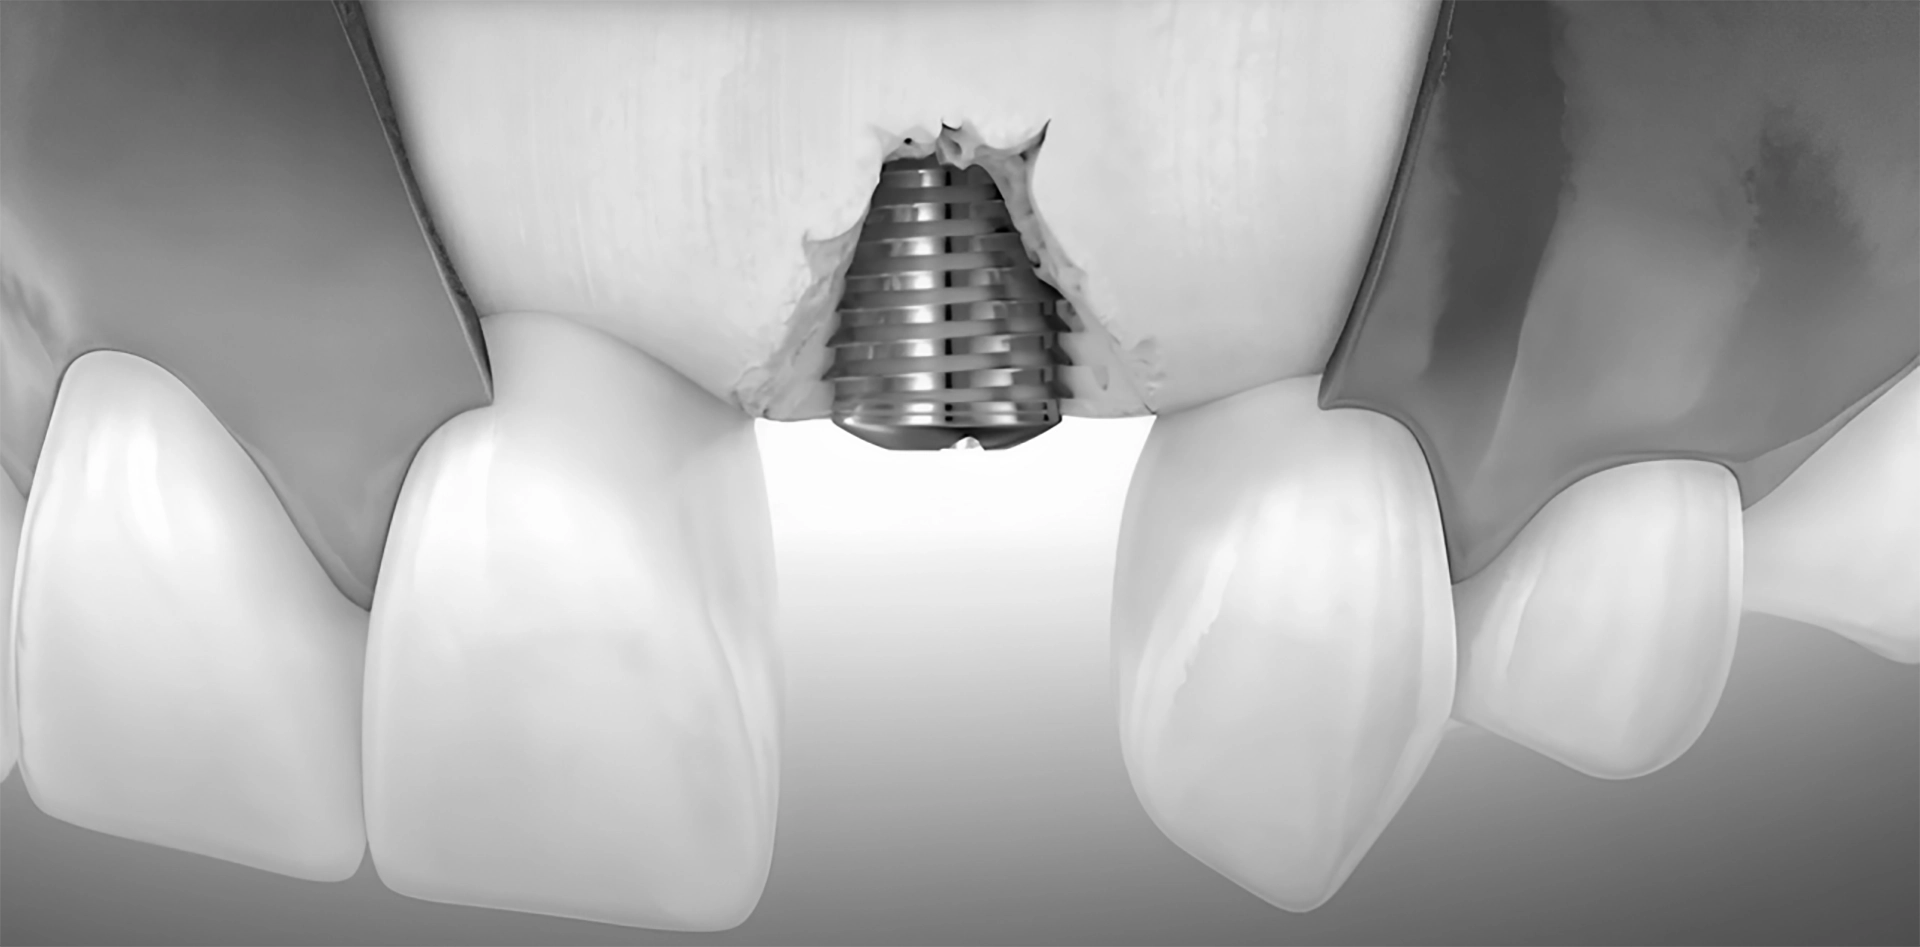

Peri-Implantitis

A more severe condition, where the infection spreads, leading to the loss of the surrounding bone.

Surgical Management

Surgery may be required for advanced cases or persistent infections. The periodontist will clean the infected area by opening a gingival flap and, if necessary, use a bone graft to regenerate lost bone around the implant.